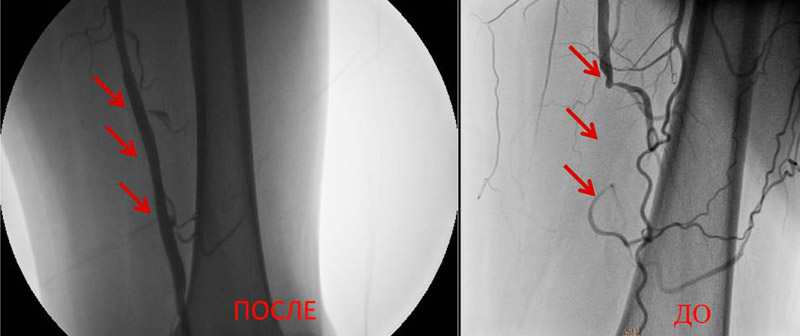

Arterial rekonstruksiyaların nəticələri